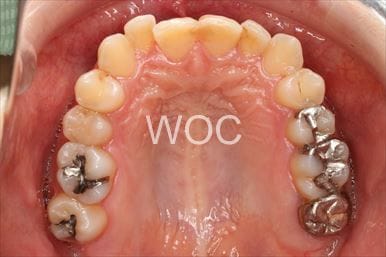

八重歯・叢生上のみ舌側矯正、下はエッジワイズ装置

上は舌側矯正を希望。ガタガタ(叢生)が強い。上顎右側中切歯・側切歯が歯科治療で連結してあったがそれを除去してから治療開始しました。

- 年齢:23歳女性

- 主訴:上下前歯のガタガタが気になる

- 基本矯正料金:103万円

- 治療期間:2年2ヶ月

- 非抜歯